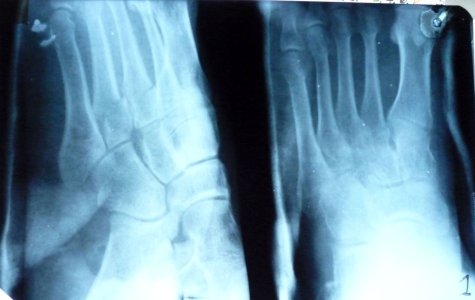

Здравствуйте, 16.10.09 в пятницу вечером на тренировке разворачиваясь на одной ноге сломал 3 и 4 плюсневые кости ,в травмопункте сделали снимки, после чего дежурный врач накладывая гипс попытался вправить смещеные плюсневые кости, но у него ничего не вышло, что видно на повторном снимке .Посоветовал с понедельника обратится в больницу по месту жительства и возможно готовится к операции.... Посмотрите пожалуйста можно ли вправить на место кости без операционного вмешательства и каковы шансы на их успешное ПРАВИЛЬНОЕ сростание.